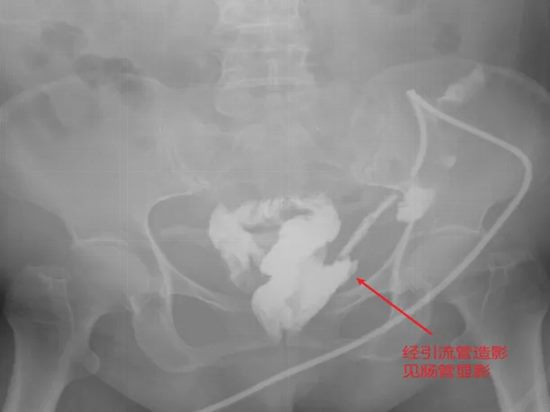

病情简述:56岁女性,两次腹膜后手术后出现降结肠瘘。

诊疗破局:按传统疗法,需先做结肠造口(挂粪袋),等半年后再做二次手术还纳。为减轻患者痛苦,团队制定“清创、控感、一期修复”三步法,实施腹腔镜下瘘切除+一期结肠端端吻合术。术后一周患者正常进食,免去了半年造口之苦。

技术体现:精准的术前评估与微创技术,让创伤最小化与疗效最大化不再是单选题。